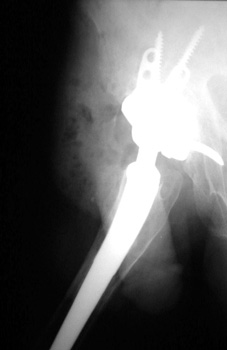

Revision arthroplasty (A). Proximal femur resected due to large amount of osteolysis (B).